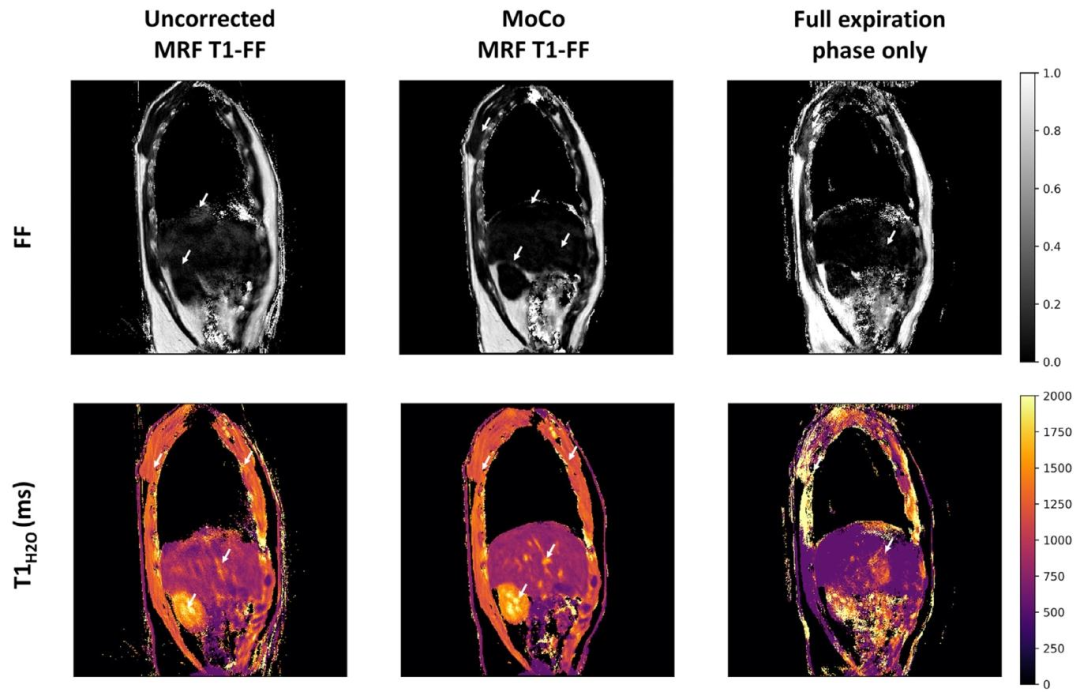

Fig. 6. Representative parametric FF and 𝑇 1𝐻2𝑂 maps obtained at one slice level in a healthy volunteer derived from the uncorrected and motion-corrected (MoCo) MRF T1-FFreconstructions, and from the MRF T1-FF data acquired during the reference respiratory phase only (corresponding to the full-expiration phase). White arrows emphasize regionswhere motion blurring, parameter estimation bias and streaking artifacts are significantly mitigated with the motion correction method.

图6 健康志愿者某一层面的代表性参数FF图和𝑇1𝐻2𝑂图,这些图像分别来源于未校正的MRF T1-FF重建结果、运动校正(MoCo)后的MRF T1-FF重建结果,以及仅在参考呼吸相位(对应完全呼气相位)采集的MRF T1-FF数据。白色箭头标注的区域显示,运动校正方法显著减轻了运动模糊、参数估计偏差和条状伪影问题。